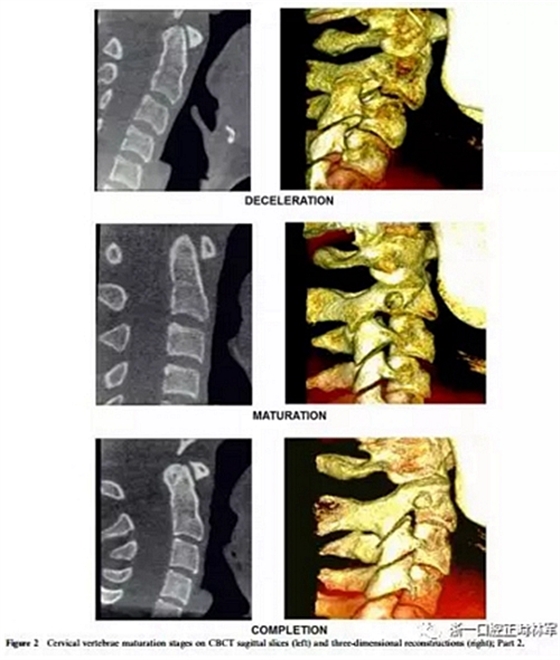

4、減速期(頸椎成熟指數(shù)-4)

預(yù)計(jì)增長10-25%。椎骨C2,C3和C4的下部邊界呈現(xiàn)明顯的凹陷,并且椎骨C3和C4的體部呈現(xiàn)近似正方形的形狀。

5、成熟期(頸椎成熟指數(shù)-5)

這對應(yīng)于椎骨成熟的最后階段,預(yù)計(jì)5-10%的增長。在椎骨C2,C3和C4上觀察到更明顯的凹陷。后者有方形的體部。

6、定型(頸椎成熟指數(shù)-6)

現(xiàn)階段增長已經(jīng)完成。椎骨C3和C4的體部具有比水平尺寸和下邊界更大的垂直,下邊界保持明確的凹陷。